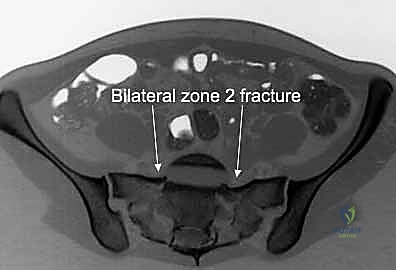

3. التصوير المقطعي المحوسب (CT Scan): وهو المعيار الذهبي (Gold Standard) لتشخيص كسور الحوض والعجز. يقوم الدكتور هطيف باستخدام تقنية إعادة البناء ثلاثي الأبعاد (3D Reconstruction) لفهم هندسة الكسر بدقة متناهية قبل الدخول إلى غرفة العمليات.

يمر عبر عظم العجز جذور الأعصاب العجزية التي تتحكم في وظائف حيوية مثل حركة الأطراف السفلية، التحكم في المثانة، ووظائف الأمعاء. أي انزياح عظمي في هذه المنطقة قد يؤدي إلى قطع أو انضغاط هذه الأعصاب، مما يسبب إعاقة دائمة إذا لم يتم تحريرها وتثبيت الكسر بدقة متناهية بواسطة خبير مثل الأستاذ الدكتور محمد هطيف.

يرتبط العجز بعظام الحرقفة عبر المفصل العجزي الحرقفي (Sacroiliac Joint)، وهو مفصل مدعوم بشبكة من أقوى الأربطة في جسم الإنسان. أي كسر أو خلع في هذا المفصل أو في عظم العجز يؤدي إلى فقدان الاستقرار الميكانيكي للجسم بالكامل.